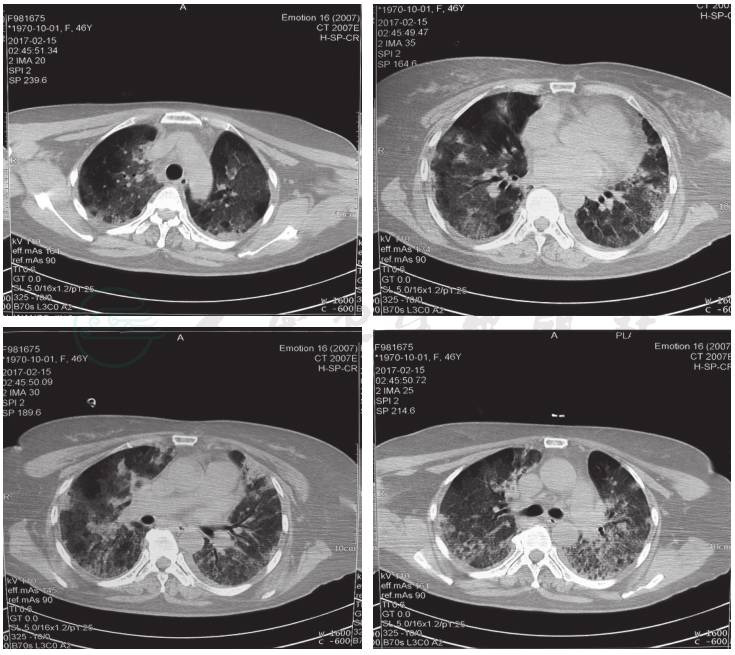

28.9mmol/L、BE 3.9mmol/L,氧合指数160。淋巴细胞亚群检测:CD3淋巴细胞亚群测定0.57,CD4淋巴细胞亚群测定0.16,CD8淋巴细胞亚群测定0.18,自然杀伤细胞(natural killer cell,NK)0.03;痰涂片:中等量革兰阴性球菌;胸部CT(2017年2月15日)提示:双肺弥漫磨玻璃和部分实变影,多发网格状高密度(图2)。

图2 胸部CT(2017-2-15):双肺弥漫磨玻璃和部分实变影,多发网格状高密度